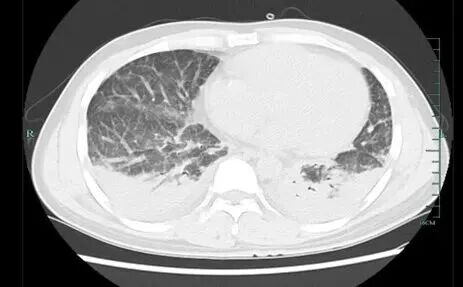

医院为壮哥做了CT检查,结果显示:双肺弥漫性病灶,血氧饱和度指标不到70%。“重症肺炎,I型呼吸衰竭。再拖下去有生命危险!”他随即被安排住院治疗,并做了基因检测,揪出了真凶——马尔尼菲篮状菌。

▲壮哥的肺部情况

这种真菌感染的症状往往很隐蔽,患者多表现为咳嗽、咳痰、胸痛,很容易被当作普通的肺炎或咽喉炎来处理。肺部影像学也缺乏特征性改变,多类似于肺炎、肺结核或肺脓肿病变。